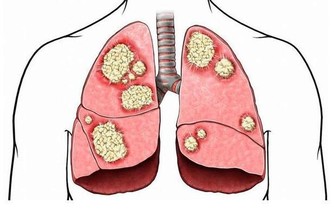

英國科學癌症研究中心研究了世界各地1000餘名30歲-50歲的癌症患者,

發現99.3%的人常年熬夜,凌晨後才會休息。

熬夜一方面會造成生物鐘紊亂,另一方面,夜間燈光會破壞人體褪黑素形成,

而這是保護人體免疫功能的重要一環,缺少它容易讓白血病、乳腺癌、前列腺癌等找上門來。